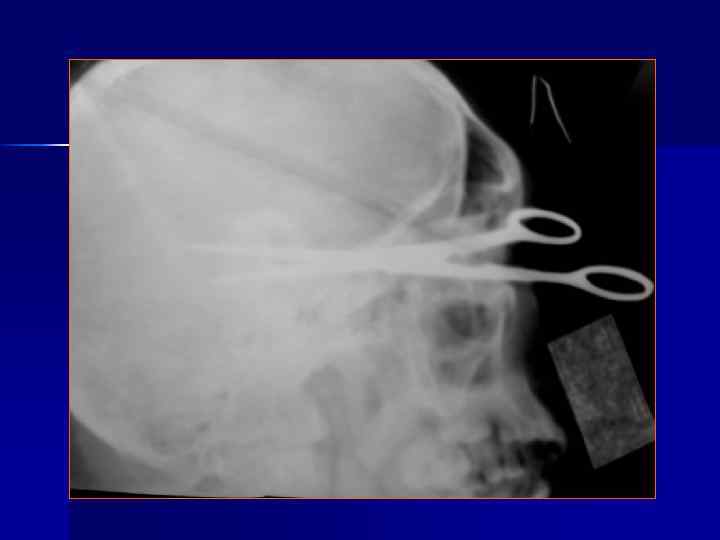

Переломы костей свода черепа N. B. -1/3 больных с тяжелой ЧМТ не имеют переломов костей. Выделяют: Линейные Вдавленные Расхождение швов Дырчатые Огнестрельные Наиболее информативна КТ, позволяющая одновременно оценить костные и внутримозговые повреждения.